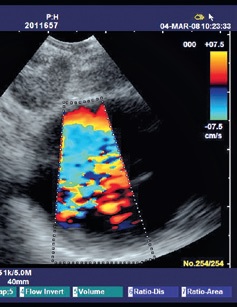

Высококачественные изображения

Модель EB-1970UK обеспечивает точную сонографическую визуализацию структур, которые невозможно выявить при обычной бронхоскопии. Возможности получения изображения включают высококачественный ультразвук, а также эндоскопические изображения высокого разрешения для детальной визуализации структур слизистых.